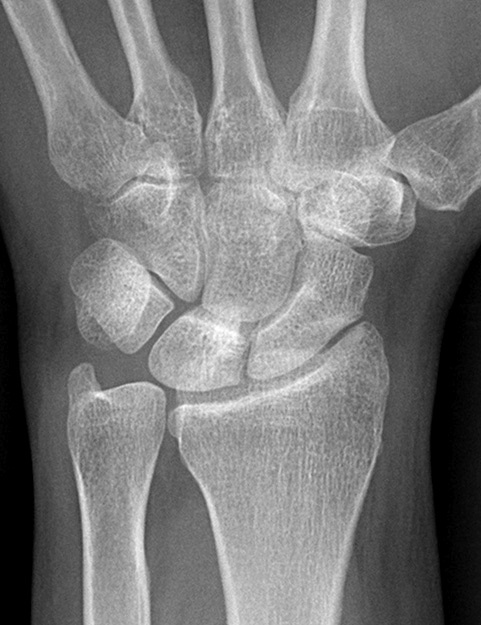

Diagnosis? Etiology?

Keinbochs

Imaging to help define collapse of lunate